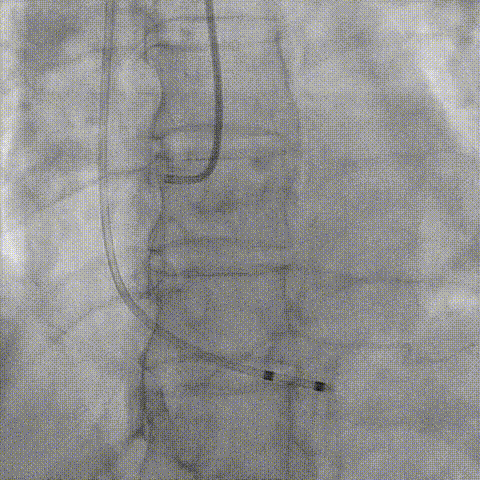

回收后调整深度,再次释放

评估左冠开口

左冠开口切线位造影

决定左冠烟囱支架保护冠脉

调整支架位置

释放冠脉支架

释放瓣膜

造影评估

支架内后扩张